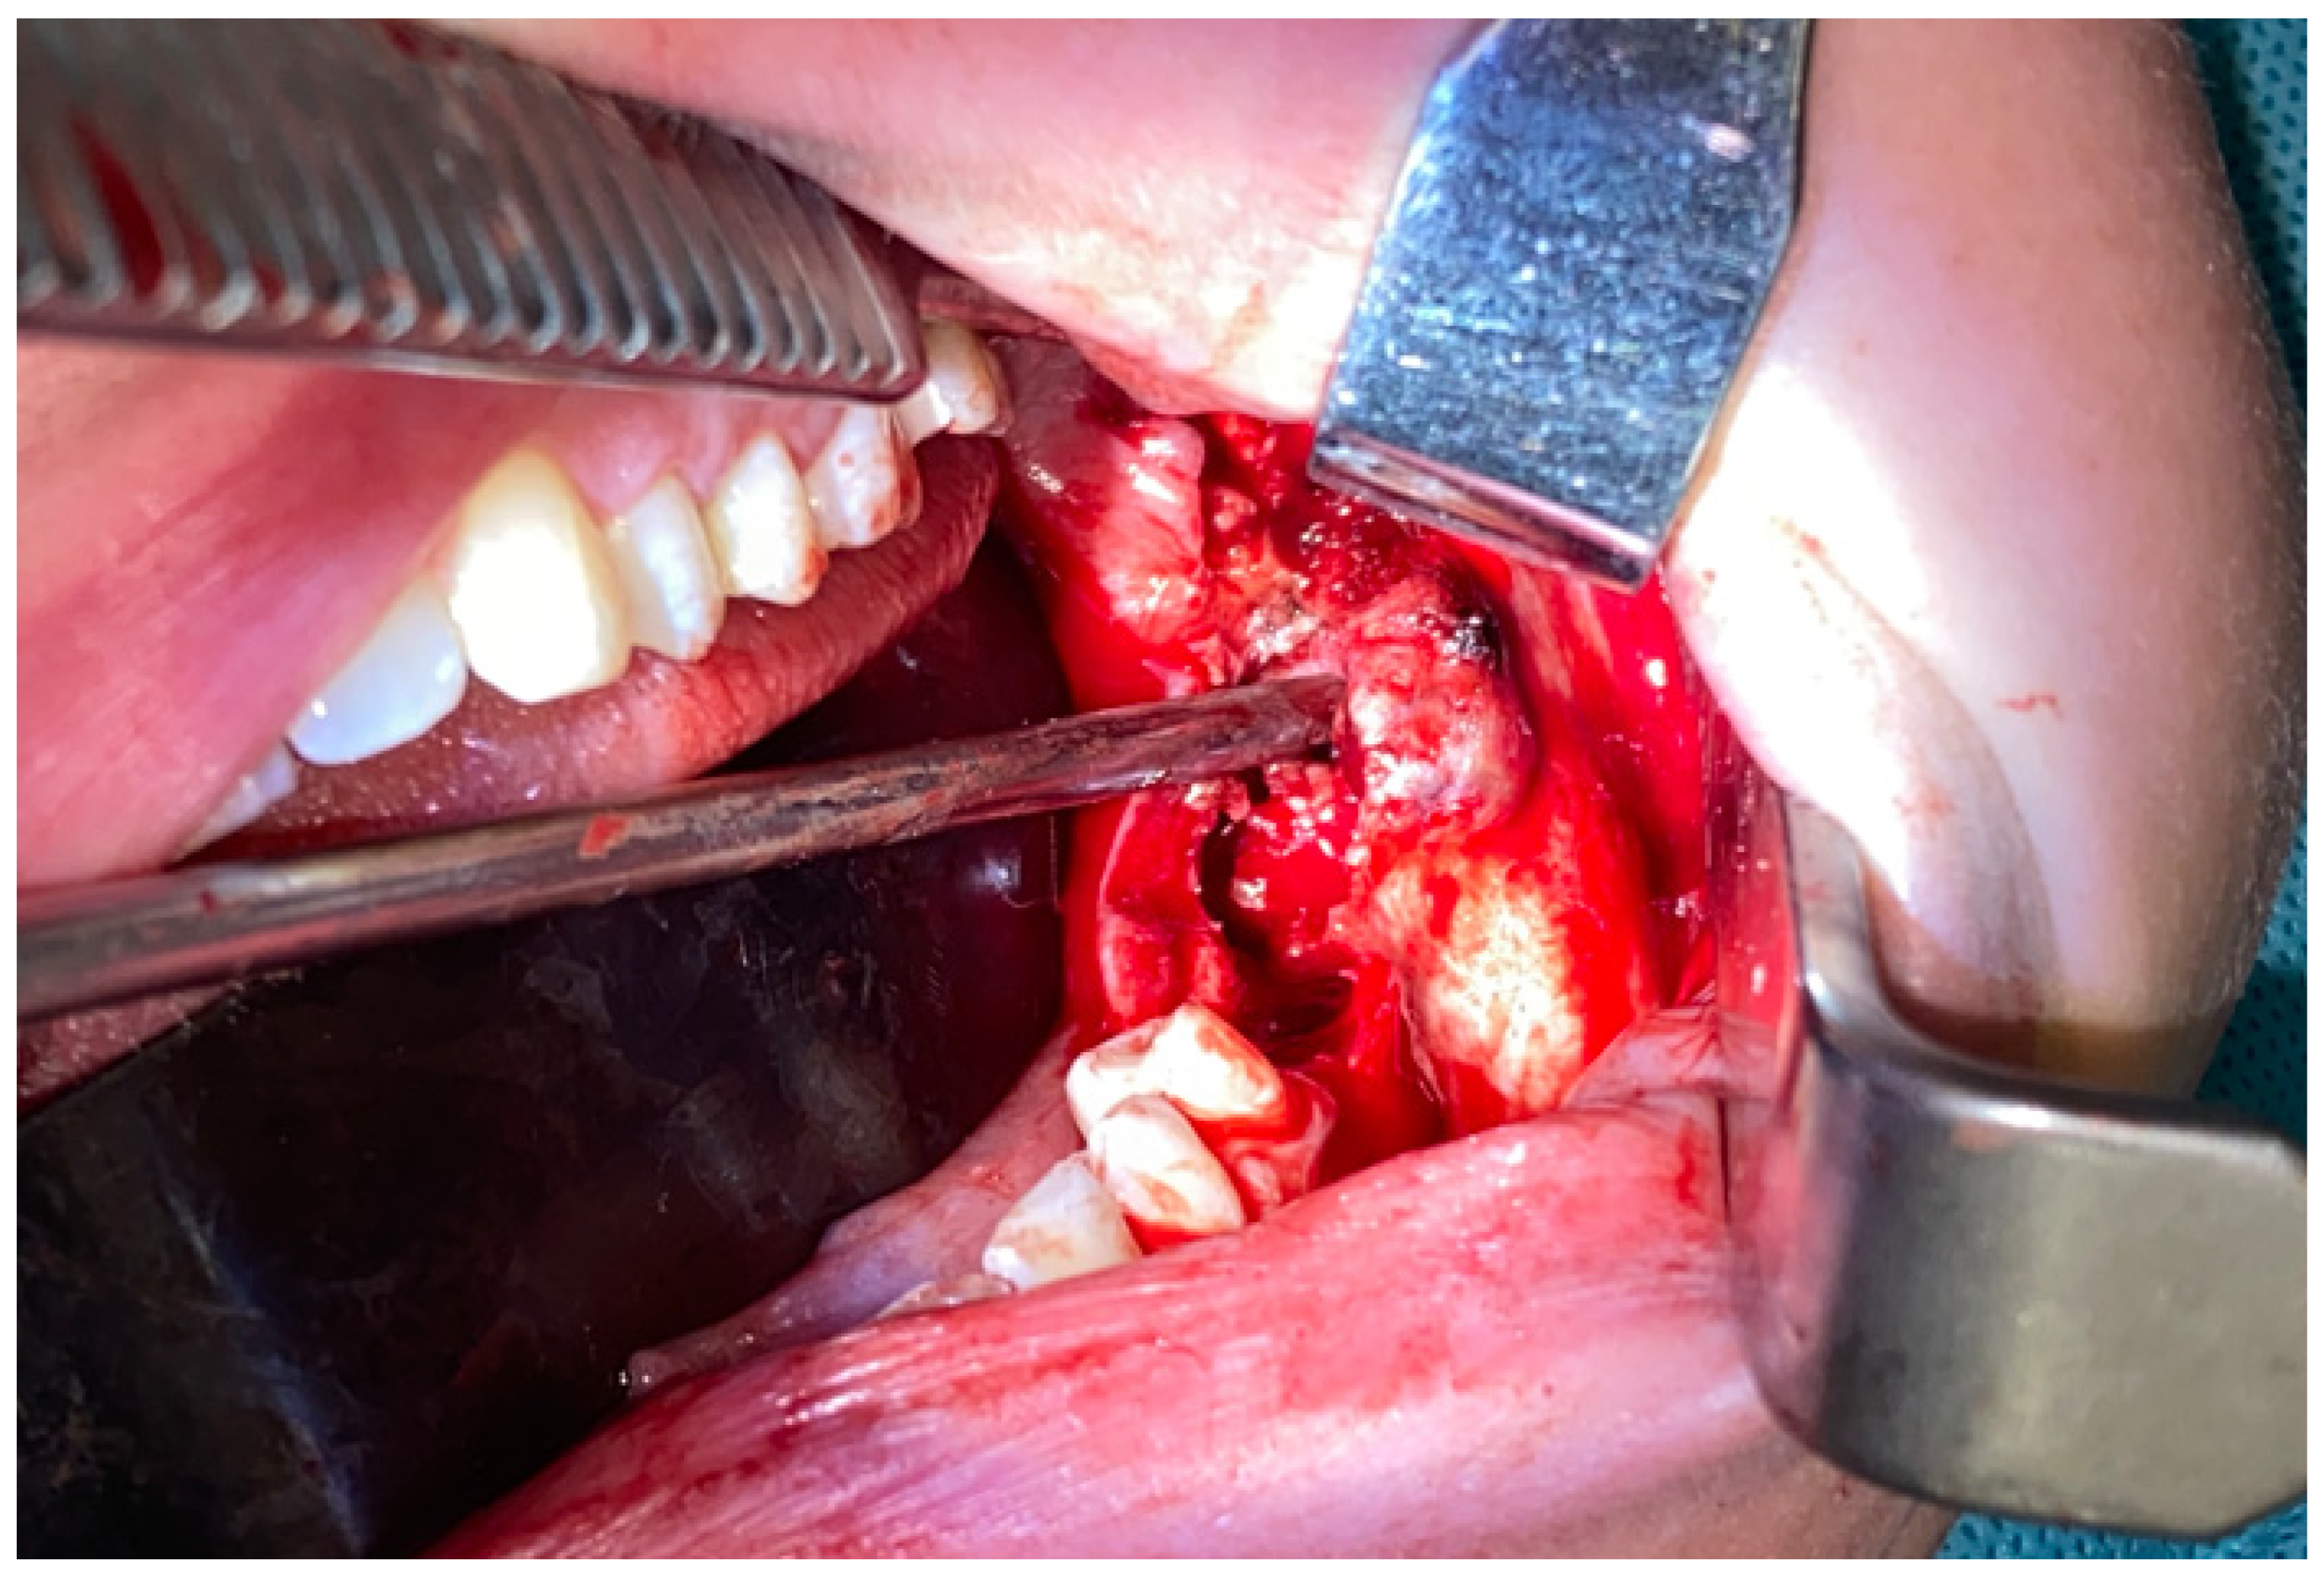

Figure 3. Intraoperative view after reconstruction and superior mandibular body marginectomy. A thin layer of intact lower mandibular border was kept and used for stable bone osteosynthesis (titanium 2.0 plates, Medartis, Basel, Switzerland) to prevent any secondary pathological fracture. The mental nerve was spared and safely retracted away (blue arrow). Surgical ostectomy was made with burrs and Lindemann drills. We avoided any unnecessary segmental resection, skin scarring, and the necessity for a bigger procedure, meaning that this surgical procedure was performed with a good overall success rate. CGCG cannot be diagnosed in any laboratory testing, and histopathology sometimes might be insufficient, where it can be misdiagnosed as BT, while radiological appearance might mimic other odontogenic cysts or tumors. On the other hand, fully grown and active BT is easily diagnosed with blood examination for calcium–phosphate markers alone. Perhaps very early in the BT formation stage, its prolonged slow growth or atypical manifestation and close relation between BT and CGCG can lead to such diagnostic dilemmas. It is worth noticing that small local lesions can be treated with nonsurgical means or local minimally invasive surgical approaches [1,2]. Some studies advice local tumor injections of calcitonin, interferon alpha, or intratumor steroids; however, the success rates vary in the known literature [3,4,5]. On the other hand, the scope of more aggressive and advanced lesions might require different surgical approaches, and in the literature, its possible outcomes vary from bone curettage and ostectomy to radical segmental osteotomies with immediate bone reconstructions or surgical debulking. Based on the following, the scope of surgery is case-driven and depends greatly on the tumor size, shape, location, and the adjacent bone condition. The presented case outlines how such a big lesion was treated by the authors with a great overall surgical success. Because of some radiological similarities between BT and CGCG, careful patient examination is mandatory, and additional bone markers should always be evaluated, and even repeated over time. It is quite important to identify any PHP or a simple CGCG lesion in good early timing to improve the patient’s general condition. Without an improved excisional biopsy in order to examine the entire specimen, its highly possible that the patient could suffer for a long time because of general status worsening caused by the effects of PHP calcium–phosphate on multiple organ systems over various intensities and time frames, causing, for example, bone osteoporosis, kidney stones, nephrocalcinosis, hypertension, cardiovascular disturbances, neuropsychiatric symptoms, pancreatitis, and muscle and joint weakness, among others [3,4,5].

Diagnostics 15 02038 g003